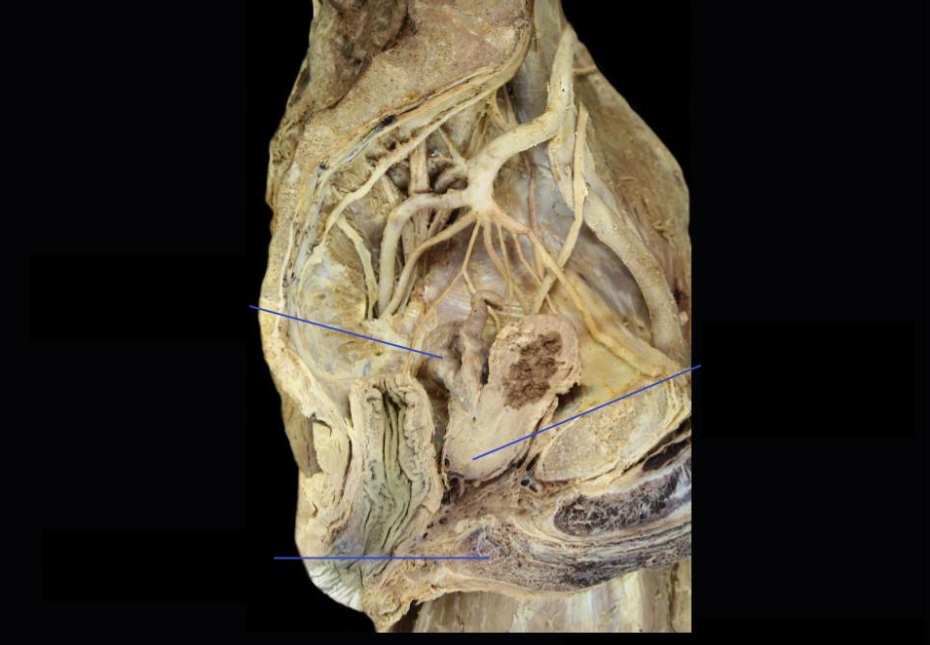

Prostate

*Prostatic venous plexus drains into Internal Iliac veins

Identify

Neurovascular Supply?

Vas Deferens

Seminal Vesicle

Side Question:

These lie at the base of the bladder

Produces citric acid and acid phosphatase

Structure found medially: vas deferens

Structure found posteriorly: rectum

Structure found inferiorly: joins with vas deferens to form ejaculatory duct

NVS?

Prostate Gland

Lobe of this structure with no glandular tissue? Anterior lobe

Upper surface of the medial lobe of this is related to trigone of bladder

Its apex lies against which structure below and is closely related to?

Urogenital diaphragm; external urethral sphincter

Its base lies against which structure and is closely related to?

Bladder; internal urethral sphincter

Beginning of Ejaculatory Duct